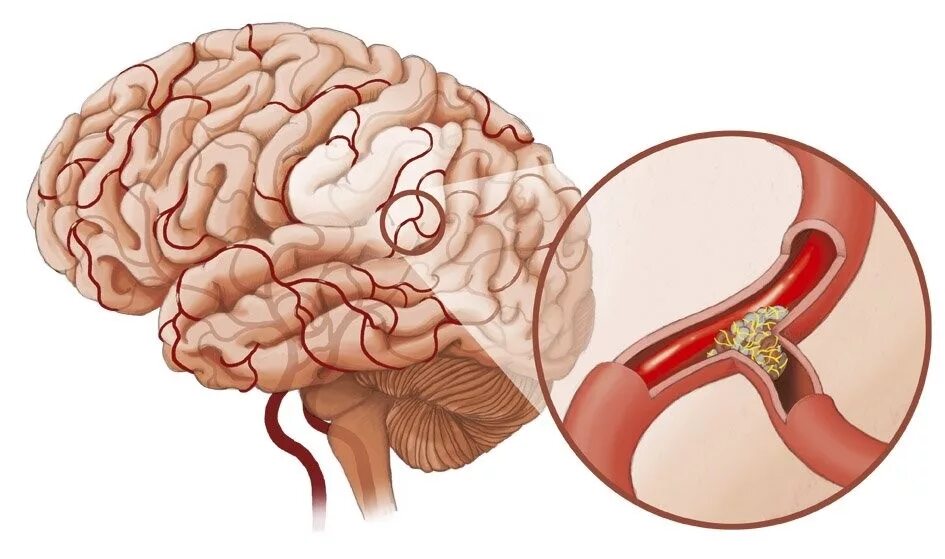

Атеросклероз головного мозга лечение у женщин